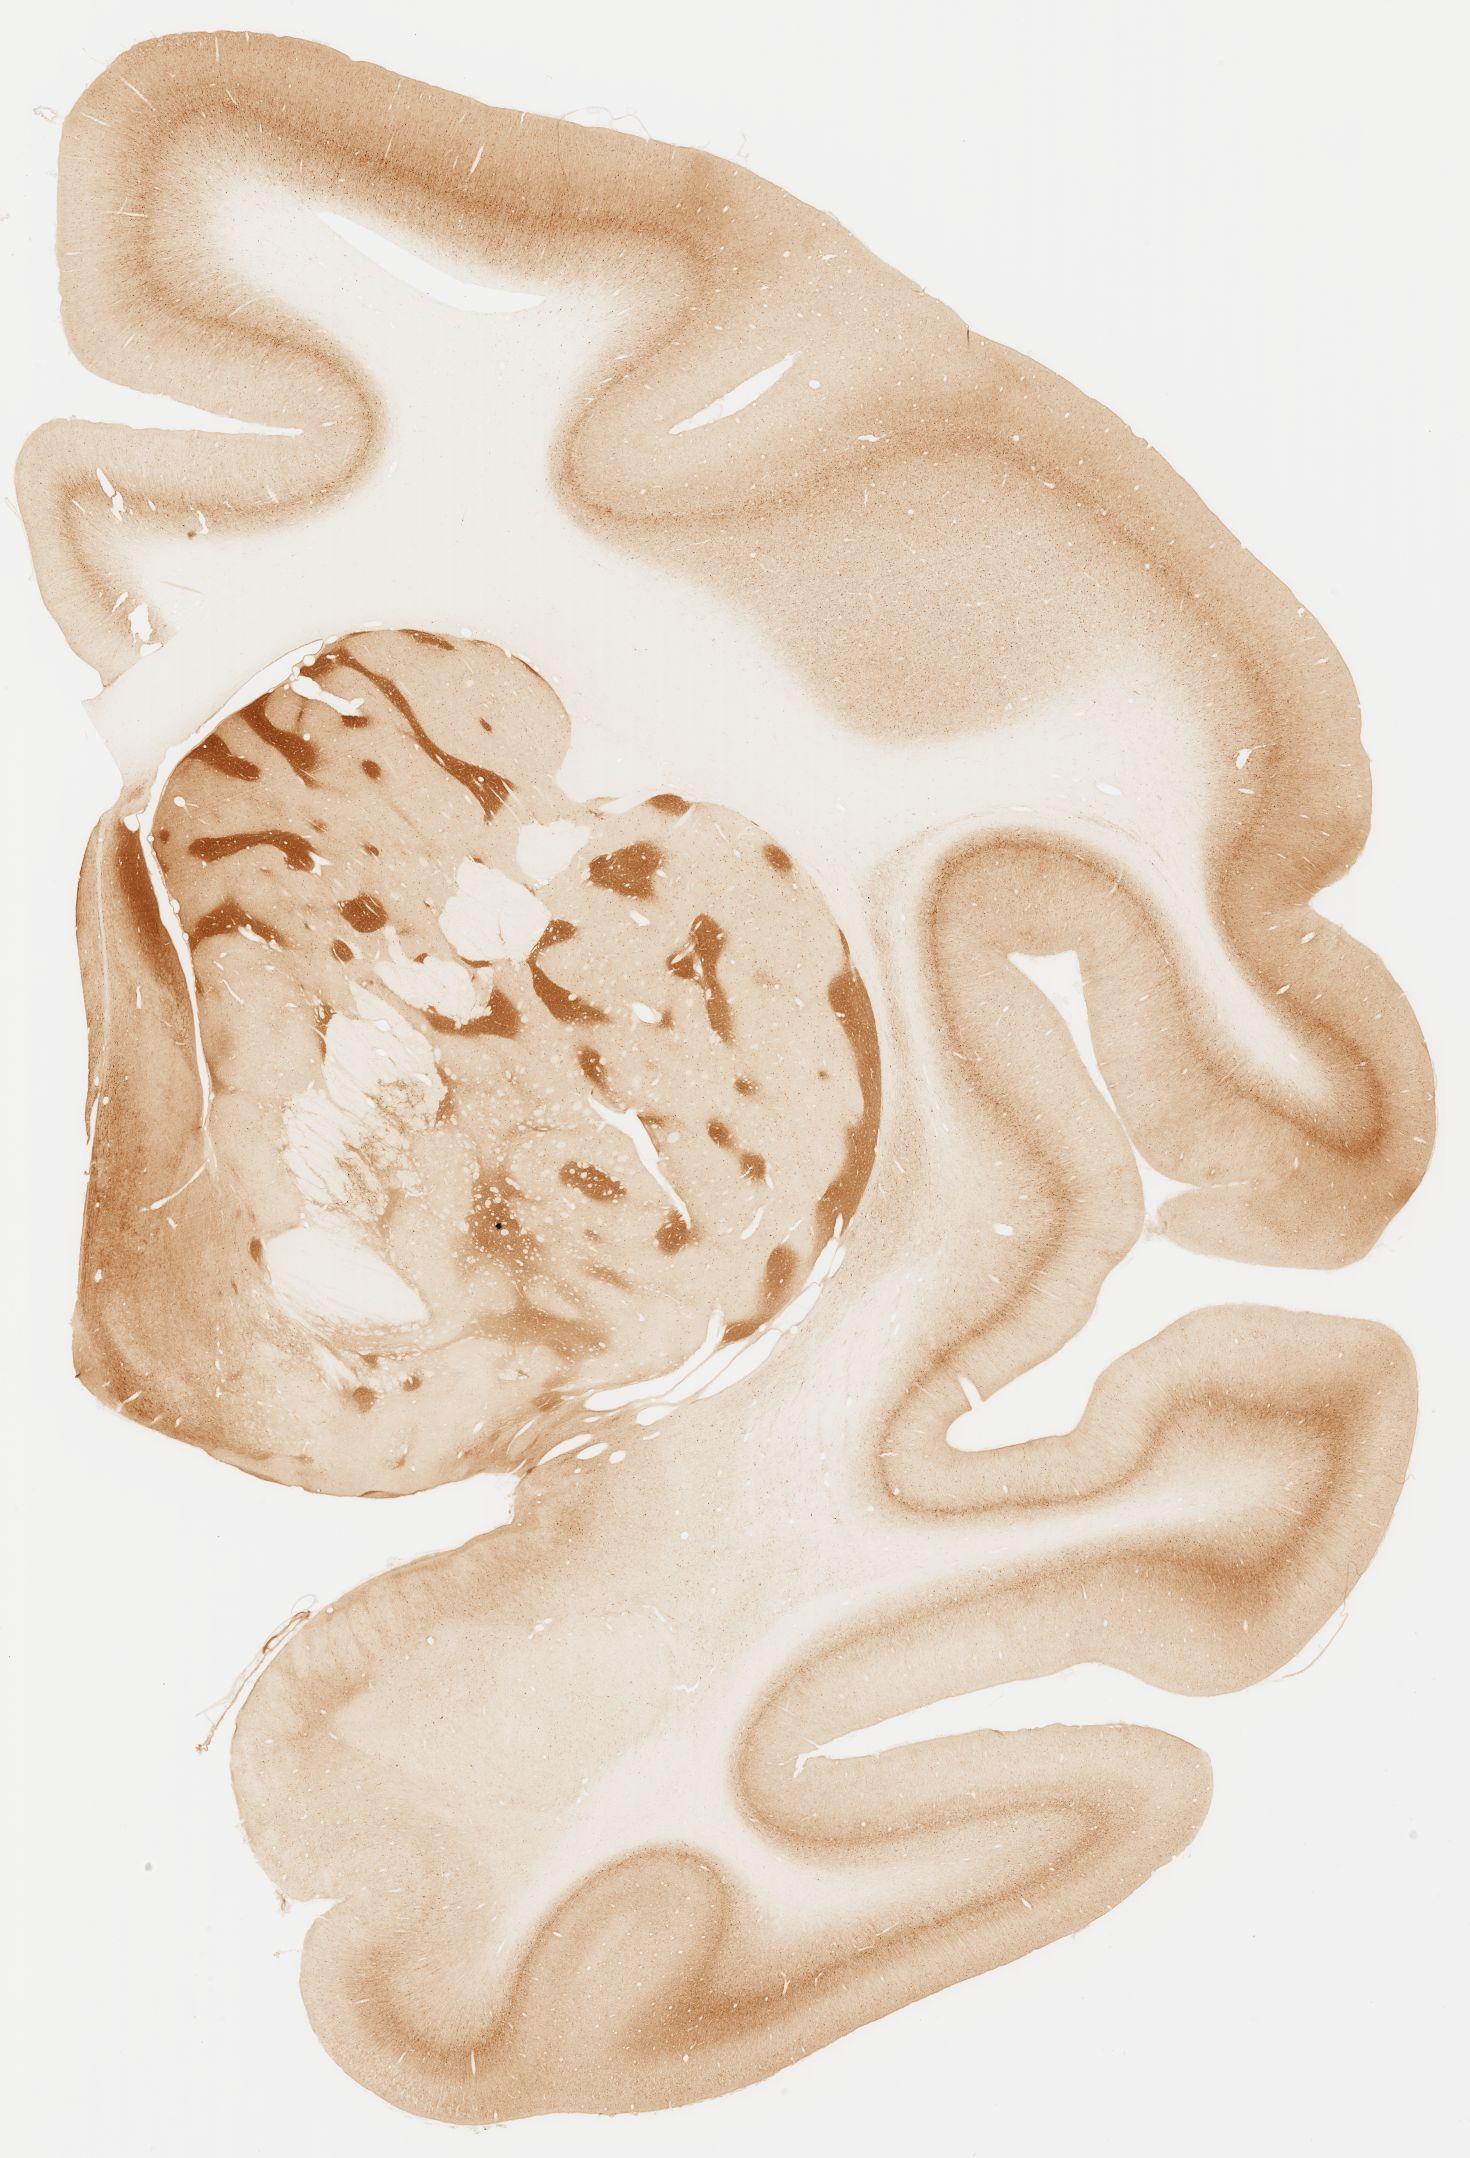

Datasets -> Macaca Fascicularis -> KChIP1, (Potassium Voltage-Gated Channel-Interacting Protein 1), coronal, immuno, Whole-Brain, adult

[ Metadata ]   ·   Source: Edward G. Jones